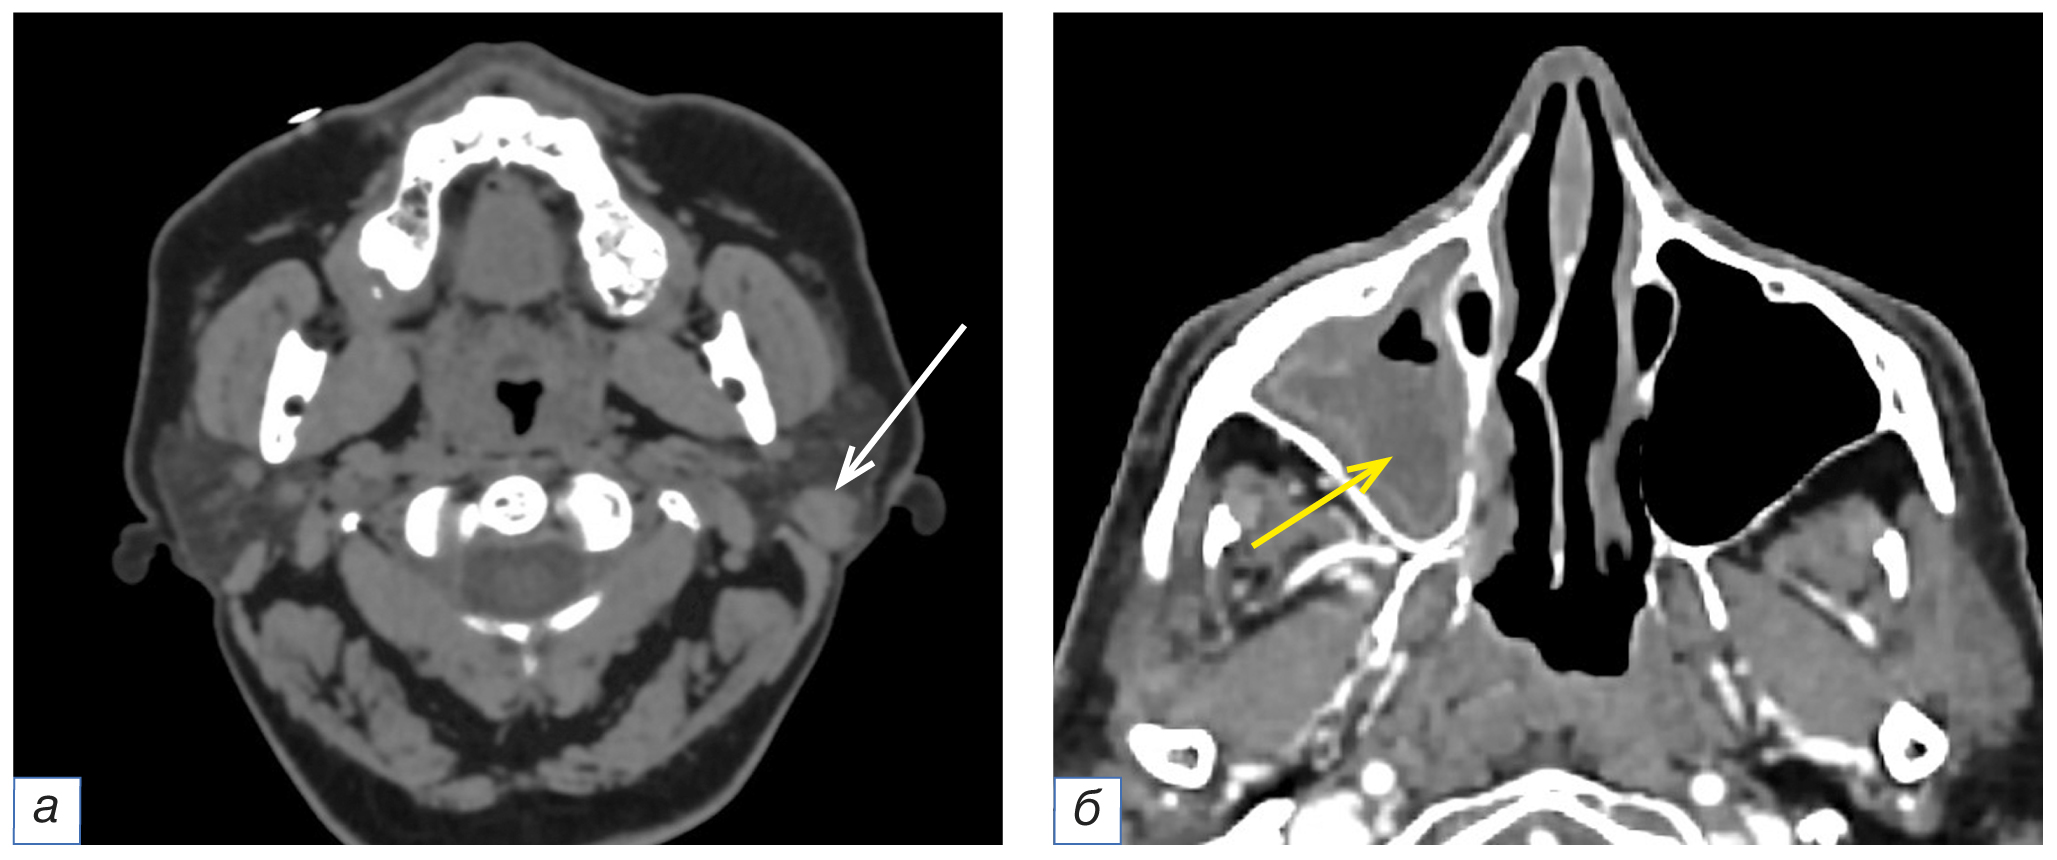

Пропуск образований околоушных слюнных желёз отмечался в 10 (16,1%) случаях, во всех из них локализация поражения была односторонняя (справа — 6, слева — 4), структура образований значимо отличалась от плотности железы, и отсутствовало распространение за её пределы (рис. 2, а). В 8 (12,9%) случаях отсутствовало упоминание патологических изменений в околоносовых пазухах, а именно в верхнечелюстных (n=6), лобных (n=1), клиновидной (n=1), и в одном случае — в сочетании с наличием образования в полости носа. В данной группе преимущественно наблюдались проявления острого или обострения хронического воспалительного процесса (n=6), а также наличие образований (n=2) (см. рис. 2, б).

Рис. 2. Фрагменты компьютерных томограмм области головы и шеи в аксиальной плоскости (а, б). У пациентки в возрасте 54 лет с подозрением на опухоль гортани в левой околоушной слюнной железе округлой формы образование с чёткими неровными контурами однородной структуры размером 13×11 мм — впоследствии гистологически верифицированная аденокарционома (а, белая стрелка). У пациента в возрасте 49 лет с диагнозом рака гортани рТ3N0M0 (комбинированная ларингэктомия) правая верхнечелюстная пазуха субтотально заполнена патологическим субстратом жидкостной плотности (б, жёлтая стрелка), стенки её с признаками гиперостоза.

Fig. 2. Computed tomograms of the head and neck, axial planes (а, б). A 54-year-old patient with a suspected tumor of the larynx has a rounded formation with clear uneven contours in the left parotid salivary gland, a homogeneous structure of a 13×11 mm size — adenocarcinoma, histologically verified subsequently (а, white arrow). In a 49-year-old patient with laryngeal cancer pT3N0M0 (combined laryngectomy), the right maxillary sinus is subtotally filled with a pathological substrate of liquid density (б, yellow arrow), its walls having signs of hyperostosis.